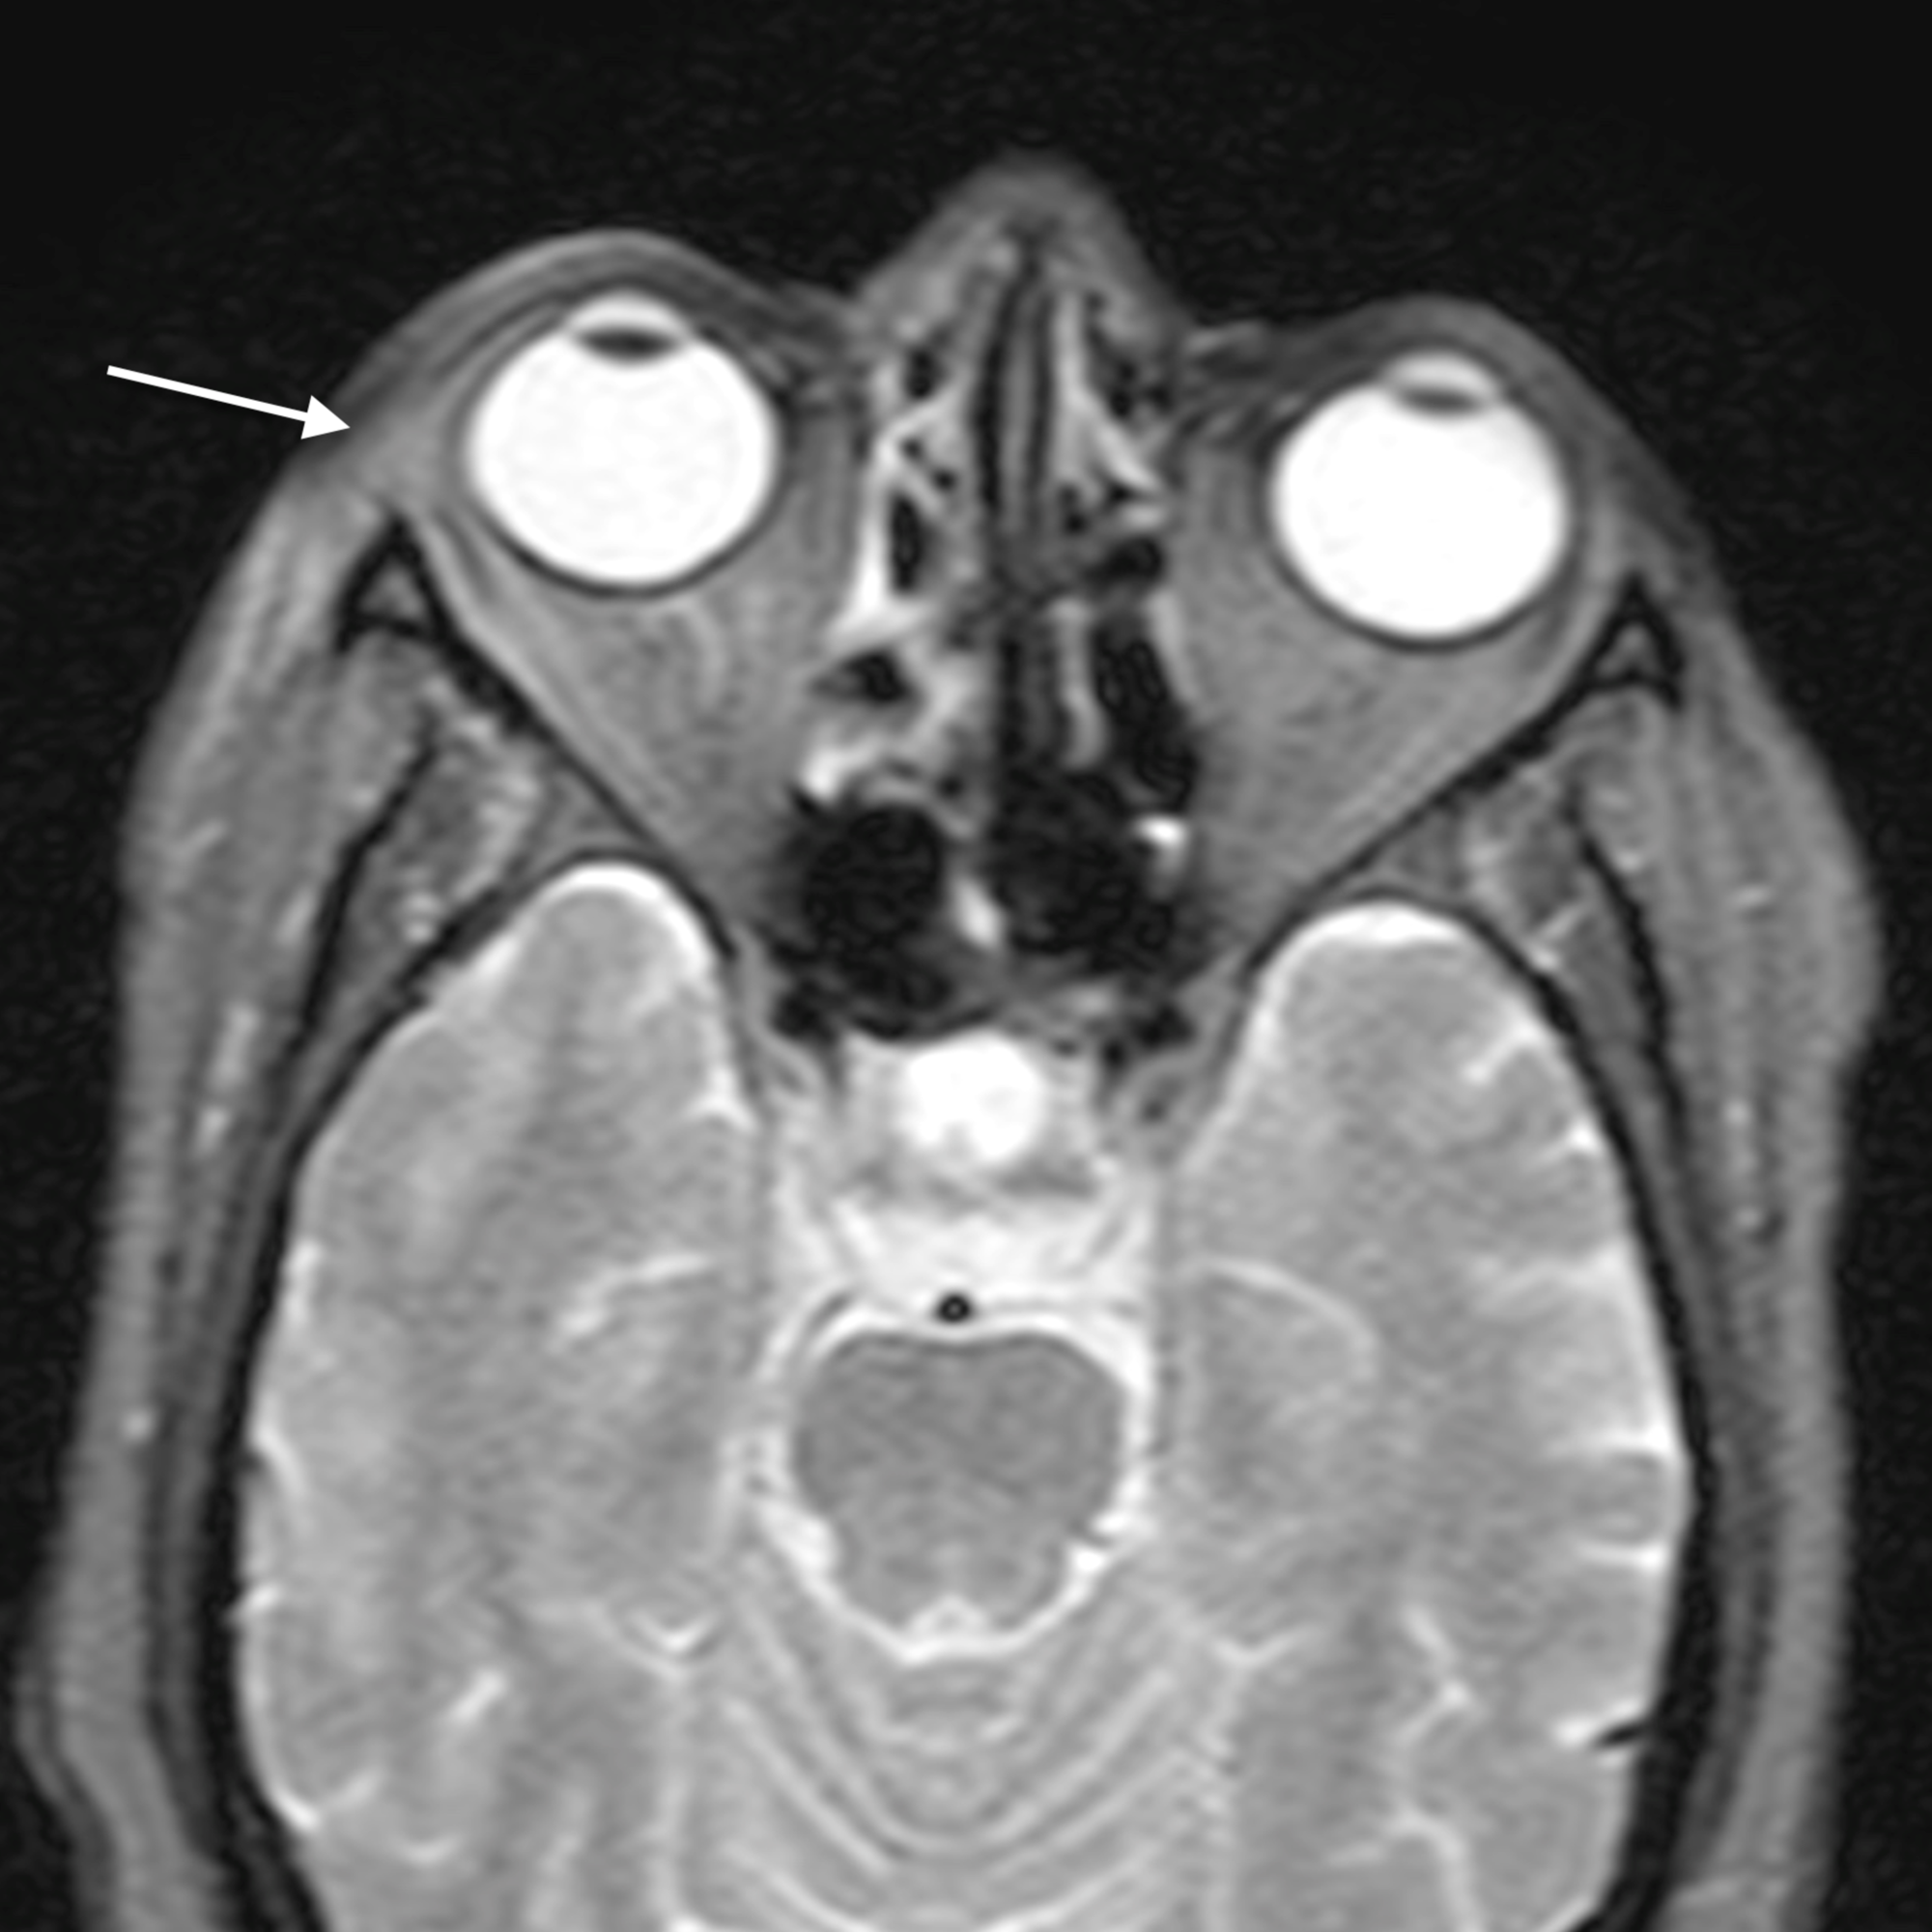

The main complications of orbital cellulitis (Figures 2-4) encountered in our study were:

1. An orbital abscess (Figures 5-6);

2. Preseptal cellulitis and abscess (Figures 7-8);

3. Periorbital cellulitis (Figures 9-10);

4. Dacryoadenitis (Figures 11-12);

5. Optic neuritis/perineuritis (Figure 13);

6. Cavernous sinus thrombophlebitis and thrombosis (Figure 14).

The most common complication of orbital cellulitis was orbital/periorbital abscess formation (eight cases, 53.3%), followed by optic neuritis (four cases, 26.67%), intracranial involvement (four cases, 26.67%), dacryoadenitis (three cases, 20%) and cavernous sinus thrombophlebitis (three cases, 20%).